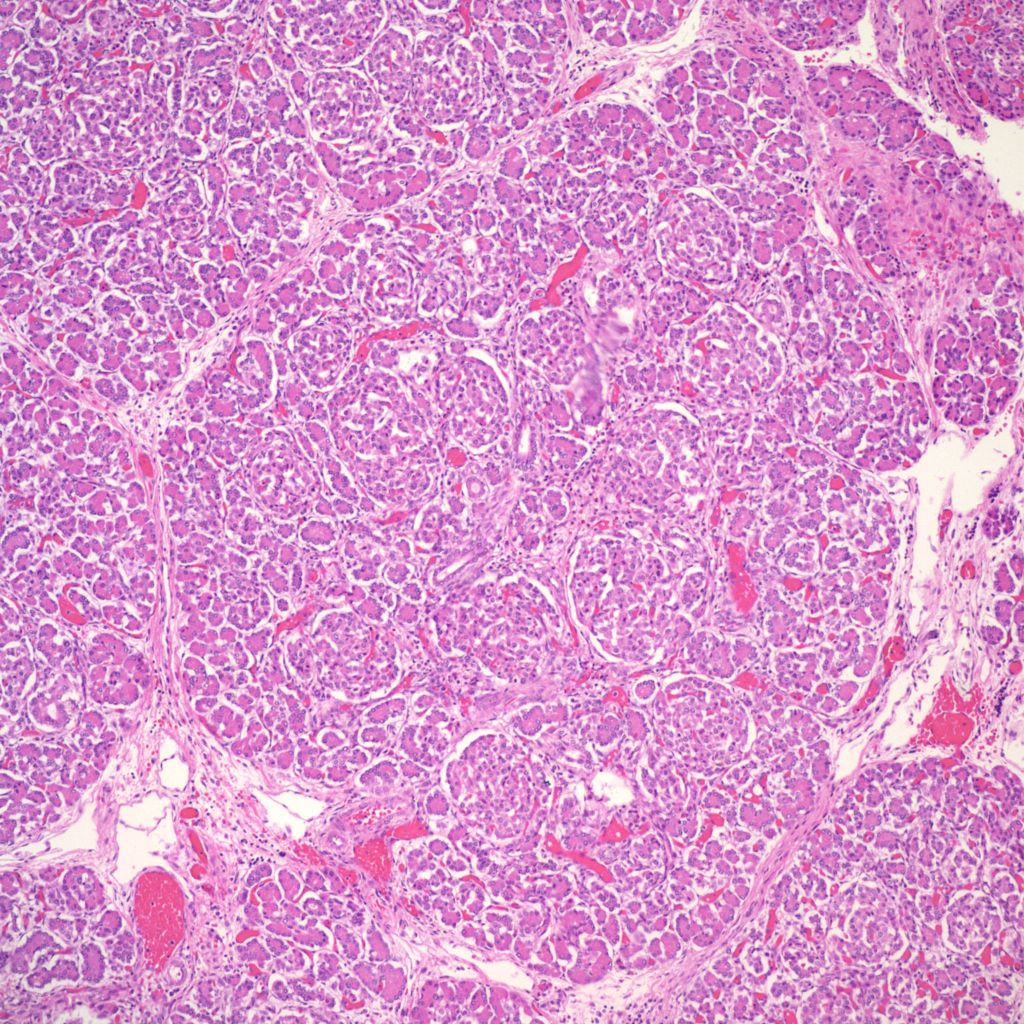

In infants of diabetic mothers, the pancreas typically demonstrates large (greater than 250 µ), plentiful islets (>7% of the pancreatic area) (Fig 5).

However, islet cell type and distribution in the pancreas is not homogenous throughout the organ and also changes with gestation. An increase in islet area may be difficult to determine without quantitative technique and comparison with matched controls for gestation and location within the pancreas. Beta cells that secrete insulin and amylin, normally make up greater than a majority of cells in an islet. Therefore, the percentage of beta cells in an islet is seldom helpful determining an overall hyperplasia of insulin secreting cells. A more reliable feature to identify evidence of increased islet response is cell hypertrophy. These hypertrophic cells are polyploid with clearly enlarged nuclei compared to surrounding cells (Fig 6).